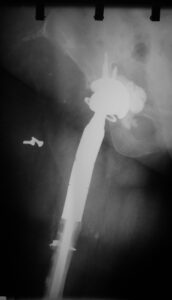

- Σε σοβαρά περιπροθετικά κατάγματα όπου υπάρχει εκσεσημασμένη απώλεια οστού και αστοχία των προηγούμενων υλικών οστεοσύνθεσης, μπορεί να αντικατασταθεί το μεγαλύτερο μέρος του μηριαίου οστού με ειδική μεγαπρόθεση που θα επιτρέψει άμεση κινητοποίηση στον ασθενή.

- Σοβαρό περιπροθετικό οστεοπορωτικό κάταγμα κάτωθεν της άρθρωσης του ισχίου.